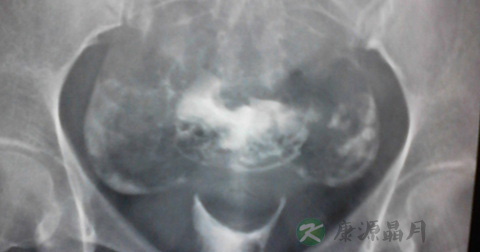

2、什么时候需要进行腹腔镜检查

在高度怀疑有输卵管周围的粘连或造影检查双侧输卵管伞端积水堵塞的时候才适合做腹腔镜检查及治疗,因为腹腔镜它毕竟是有创伤的。